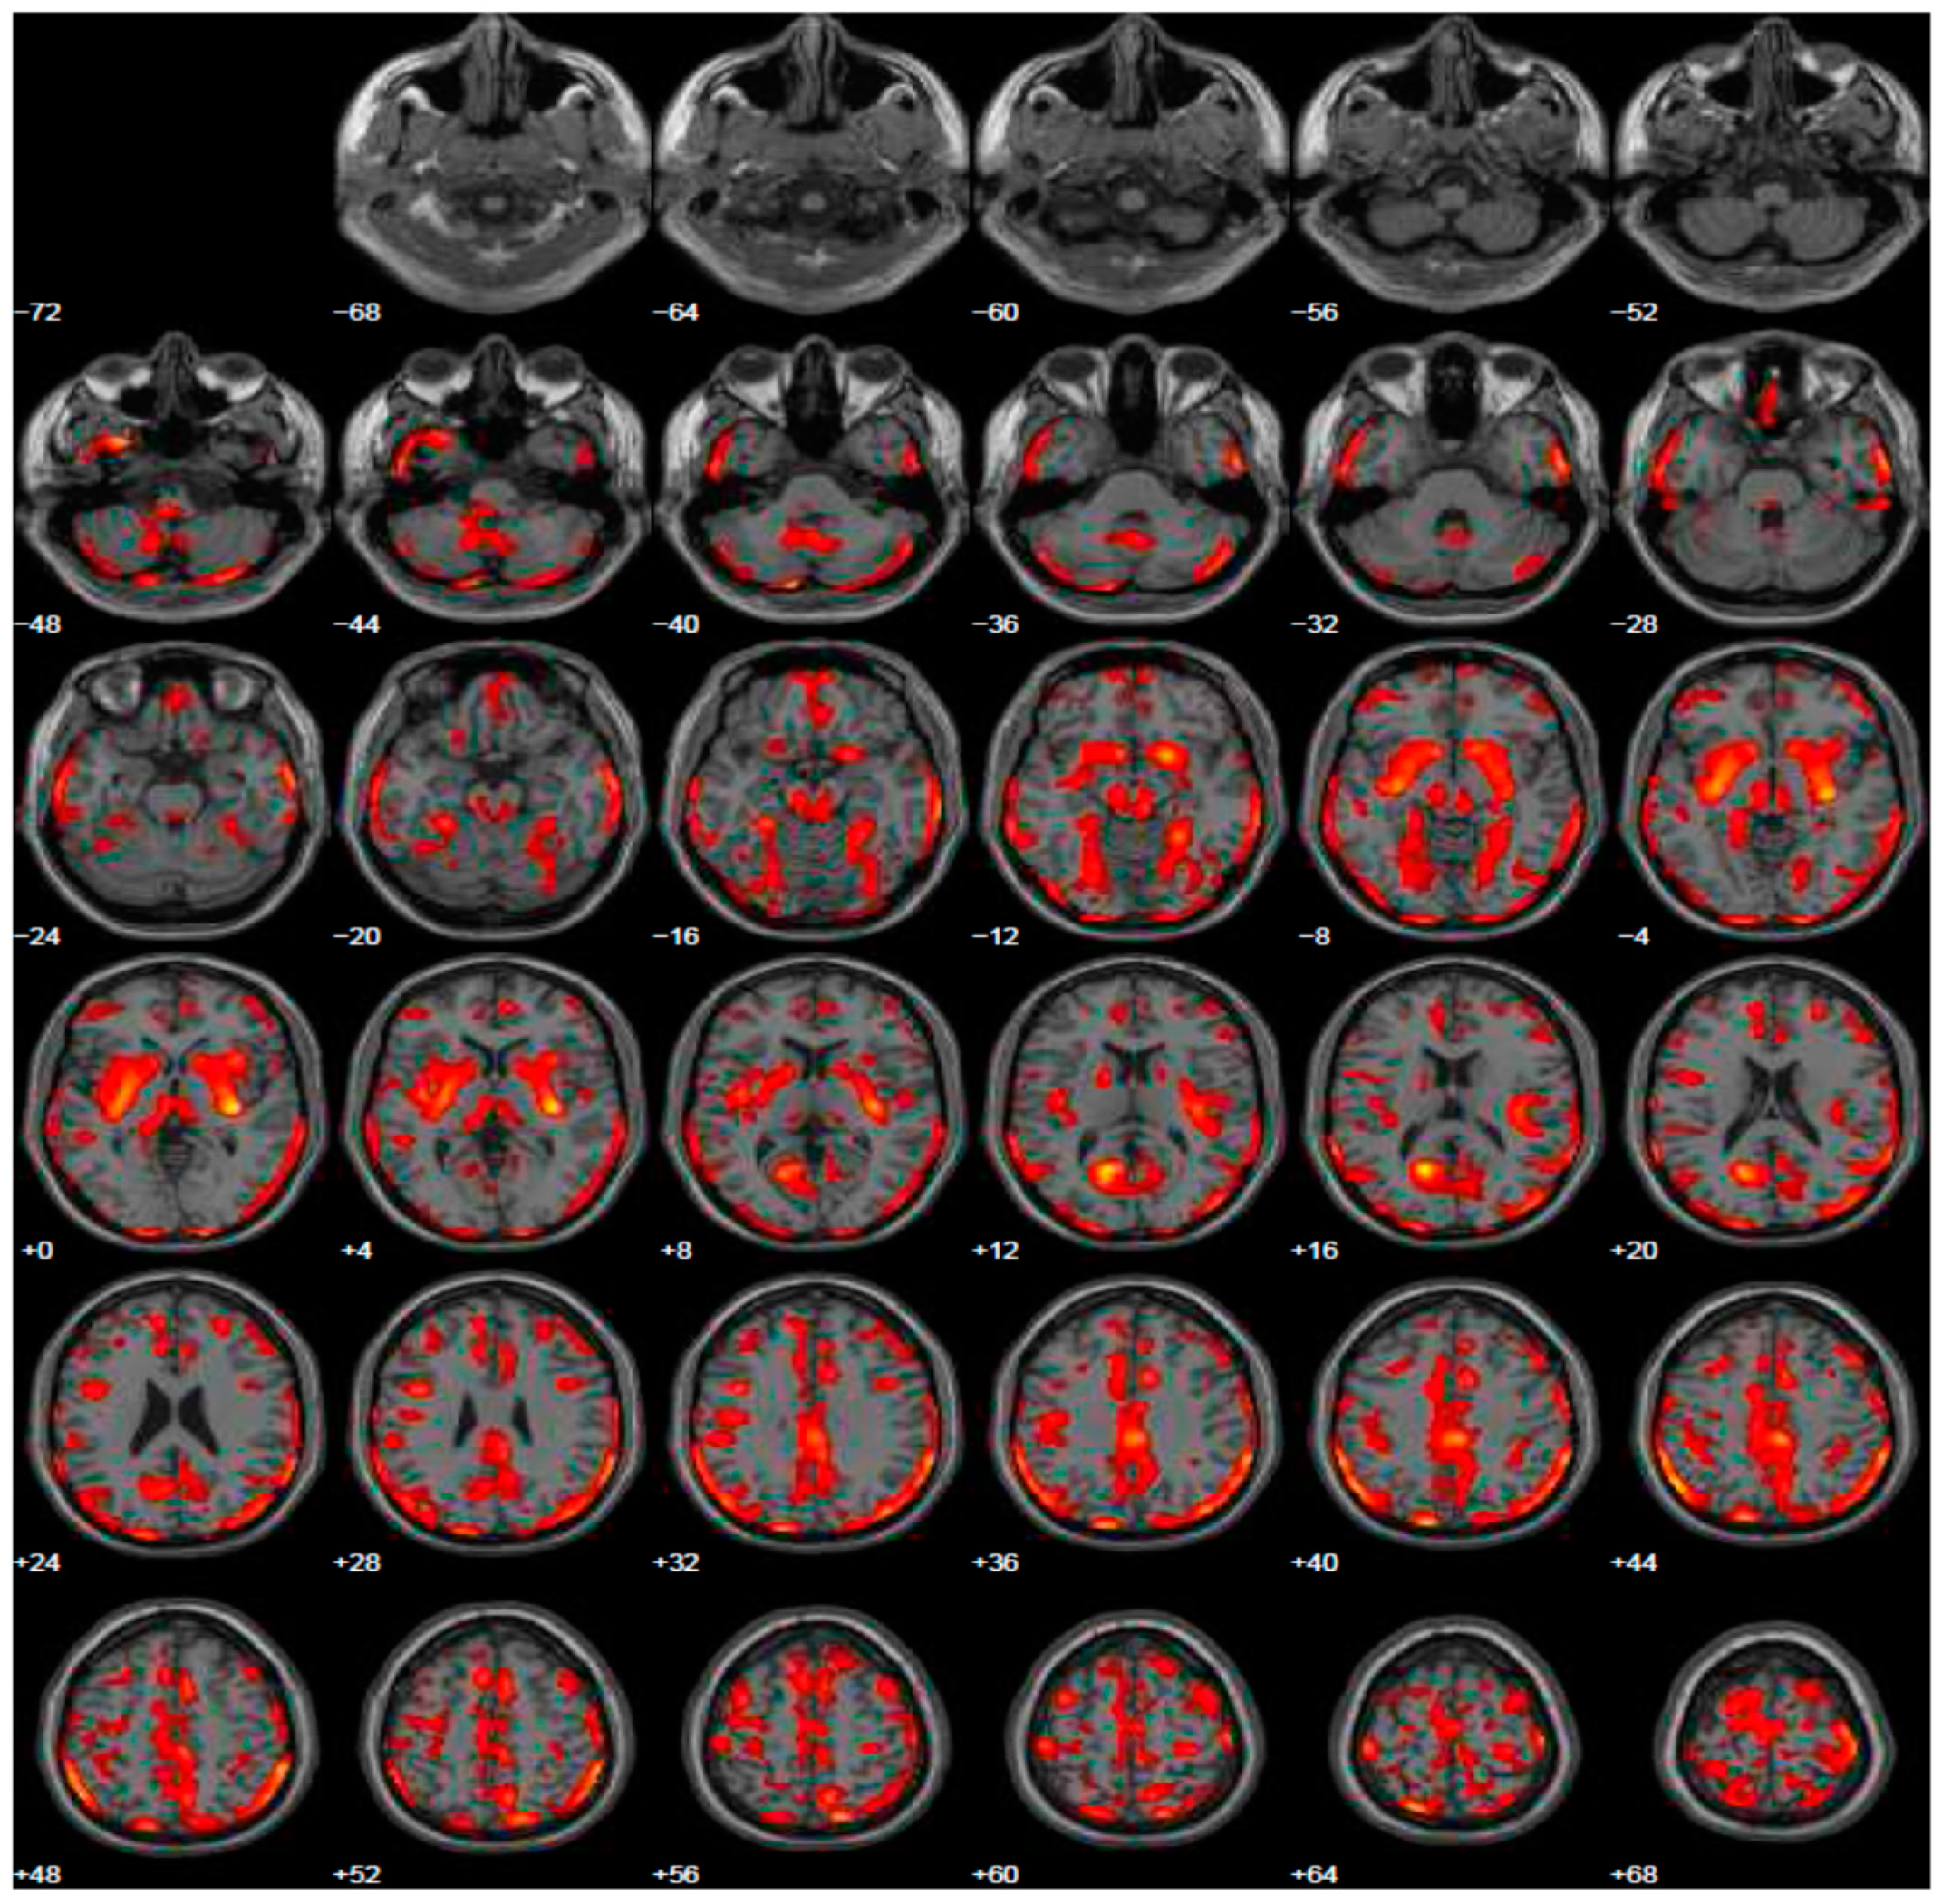

Given psychiatric symptoms reported, we changed the current treatment starting L-dopa and prescribed the FDG-PET, because of the severe anxiety induced in family members of this young PD patient. FDG-PET showed extended hypometabolism in the right and left inferior frontal gyrus and in part of the prefrontal lateral areas (Figure 2). A further cognitive assessment by MMSE remained normal and even the second level of neuropsychological evaluation resulted normal. After the prescription of L-dopa at the dosage of 300 mg daily, motor symptoms disappeared and patient’s wife reported a profound improvement of behavior, with disappearance of ICDs.

Figure 2.

Brain PET with 18F-FDG. Images highlight brain regions consistently found the analysis (Statistical Parametric Mapping software SPM 5 (p = 0.05). Diffuse hypometabolism in the left middle temporal gyrus, right and left inferior frontal gyrus, left middle frontal gyrus, left posterior cingulate, left inferior parietal lobule, right lentiform nucleus (putamen), right caudate head, left thalamus, left parahippocampal gyrus, right red nucleus (midbrain), left cerebellum pyramis, right and left cerebellum inferior semi-lunar lobule, right and left cerebellum posterior lobe tuber, right cerebellum anterior lobe nodule, left cerebellar tonsil.